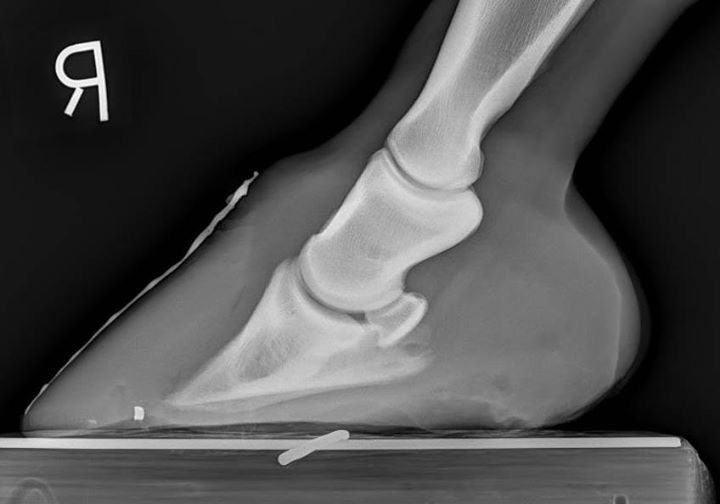

- We can help you decide the next best step in the course of treatment or diagnostics.

- For example, we can help you make the decision whether the patient needs to go to surgery, an ultrasound, etc.

- We can help you with unique positioning or procedures that can help with the diagnosis.

- Having all of your studies interpreted is taking the quality of medicine you practice to the next level.